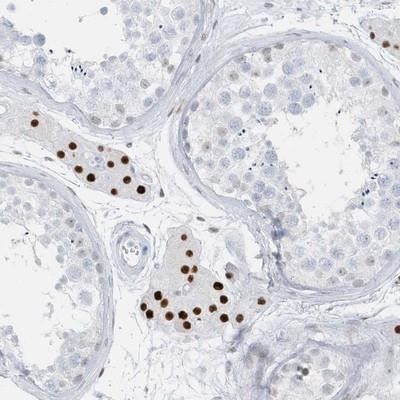

- Main image

- Experimental details

- Immunohistochemistry-Paraffin: AP000322.53 Antibody [NBP1-91141] - Staining of human testis shows strong nuclear positivity in cells in seminiferus ducts.